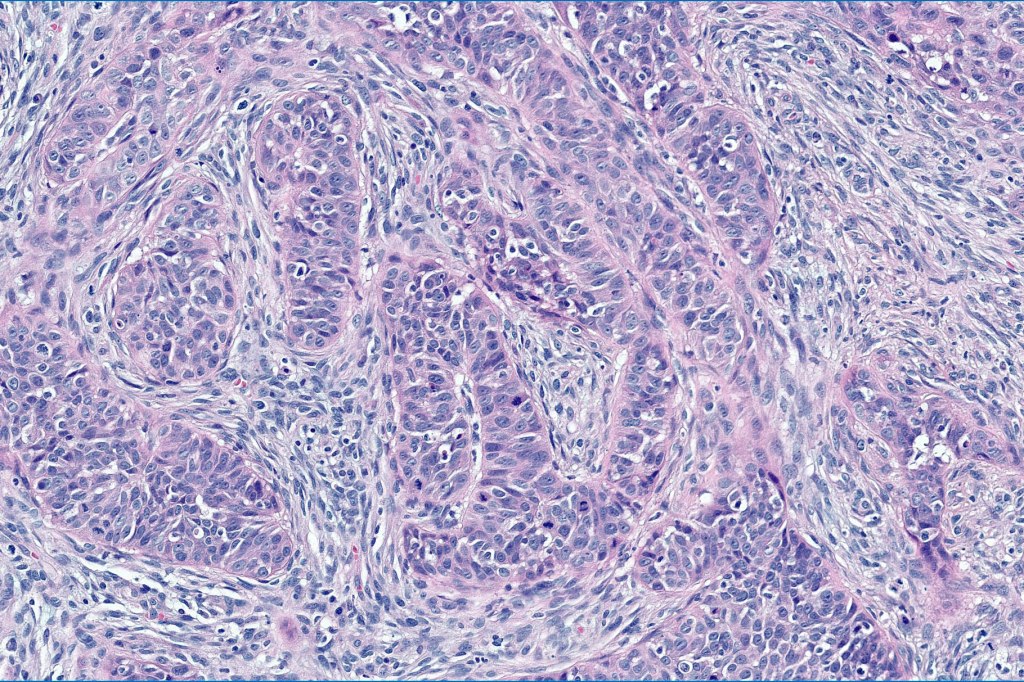

•Trichoblastic sarcoma is characterized by readily recognizable trichoblastoma associated with a high grade sarcomatous element

•Trichoblastic carcinosarcoma combines trichoblastic carcinoma & sarcoma